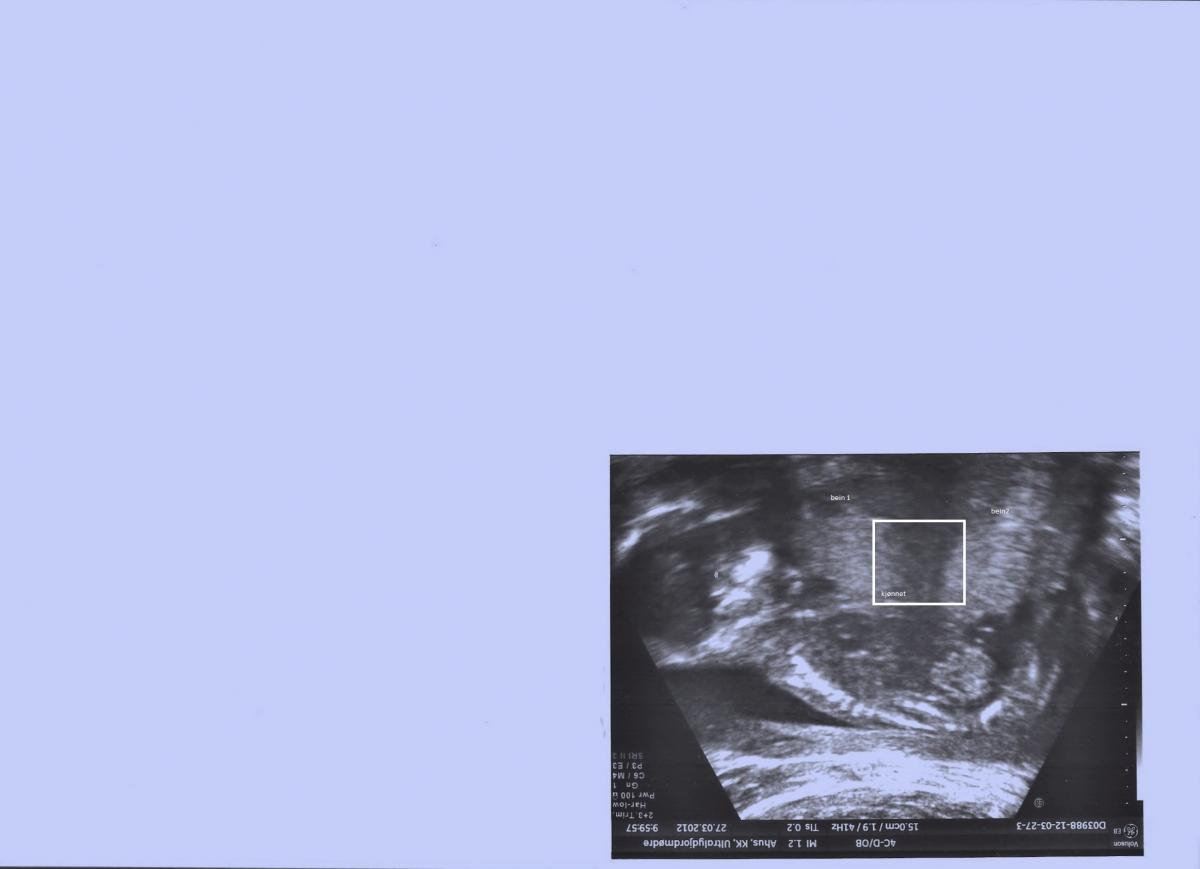

missy83 Skrevet 6. juni 2012 #1 Skrevet 6. juni 2012 Hei Jeg har vært på to ultralyd i uke 18 og 19. Dette bilde er fra uke 18. Jordmor var veldig usikker på kjønnet. Er det noen som klarer å se hva det blir?????? Er i uke 29 nå.

missy83 Skrevet 6. juni 2012 Forfatter #6 Skrevet 6. juni 2012 Det var ikke lett å se på det bildet. Her er entil der jeg har skrevet på hvor beina er og evt kjønnet. Jeg synes jeg ser en tut, men blir veldig usikker når legen sa kanskje jente på 2 ultralyd.